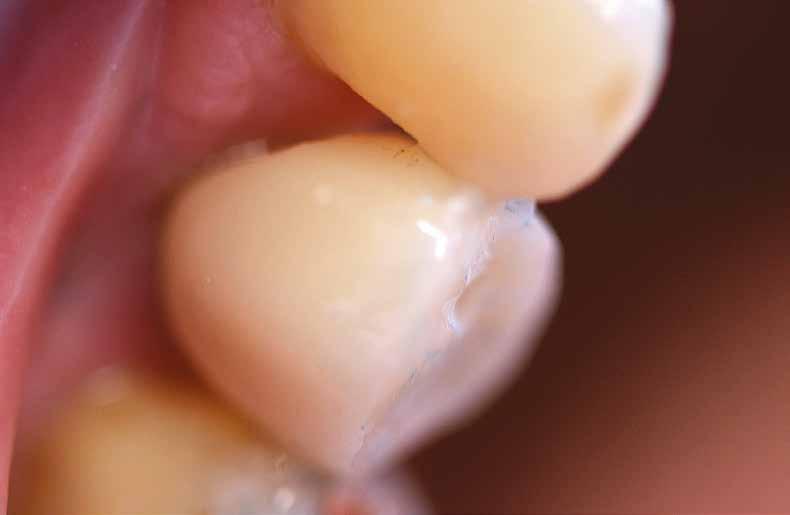

5. ábra: Az eltávolított implantátum egy vékony metszete: az implantátumhoz spongiózus csontszövet és lágyszövet kapcsolódott középen és kresztálisan; a felső három-négy menet kb. 70%-át fedte csont kresztálisan; laza kötőszövetet, valamint perifériálisan erekben gazdag, laza kötőszövetet találtunk; kresztális csont-fragmentumokat lehetett felfedezni. További nagyításnál szoros csont-implantátum kapcsolatot figyeltünk meg. 6. ábra: Nagyobb nagyítás: a csont-implantátum kapcsolat nagyon szoros volt, különösen kresztálisan, ahol 5-10 nm széles, amorf határterület volt látható; lamelláris csont, élő oszteocitákkal; oszteociták az implantátum felszíne körül; a külső csont felszínén oszteogenezis jeleit figyelhettük meg oszteoblasztokkal és oszteoid üledékkel; perifériálisan több desmális oszteogenezis volt megfigyelhető oszteoblaszt kondenzációk kialakulásával; oszteoidokkal és érett, lemezes csont-töredékekkel; sejtekben és erekben gazdag kötőszövet masztocitákkal és zsírsejtekkel; az implantátum környezetében számos eret láthattunk; néhány helyen még apró oszteoklasztok is voltak; kresztálisan nem volt rezorpcióra utaló jel; sem nekrózist, sem infiltrációt nem láttunk.

7. ábra: Az eltávolított implantátum mikroszkópos képe megfelelő csont-implantátum kapcsolatot mutat és sikeres oszteogenezist. 8. ábra: Az eltávolított implantátum mikroszkópos képe megfelelő vaszkularizációt mutat.